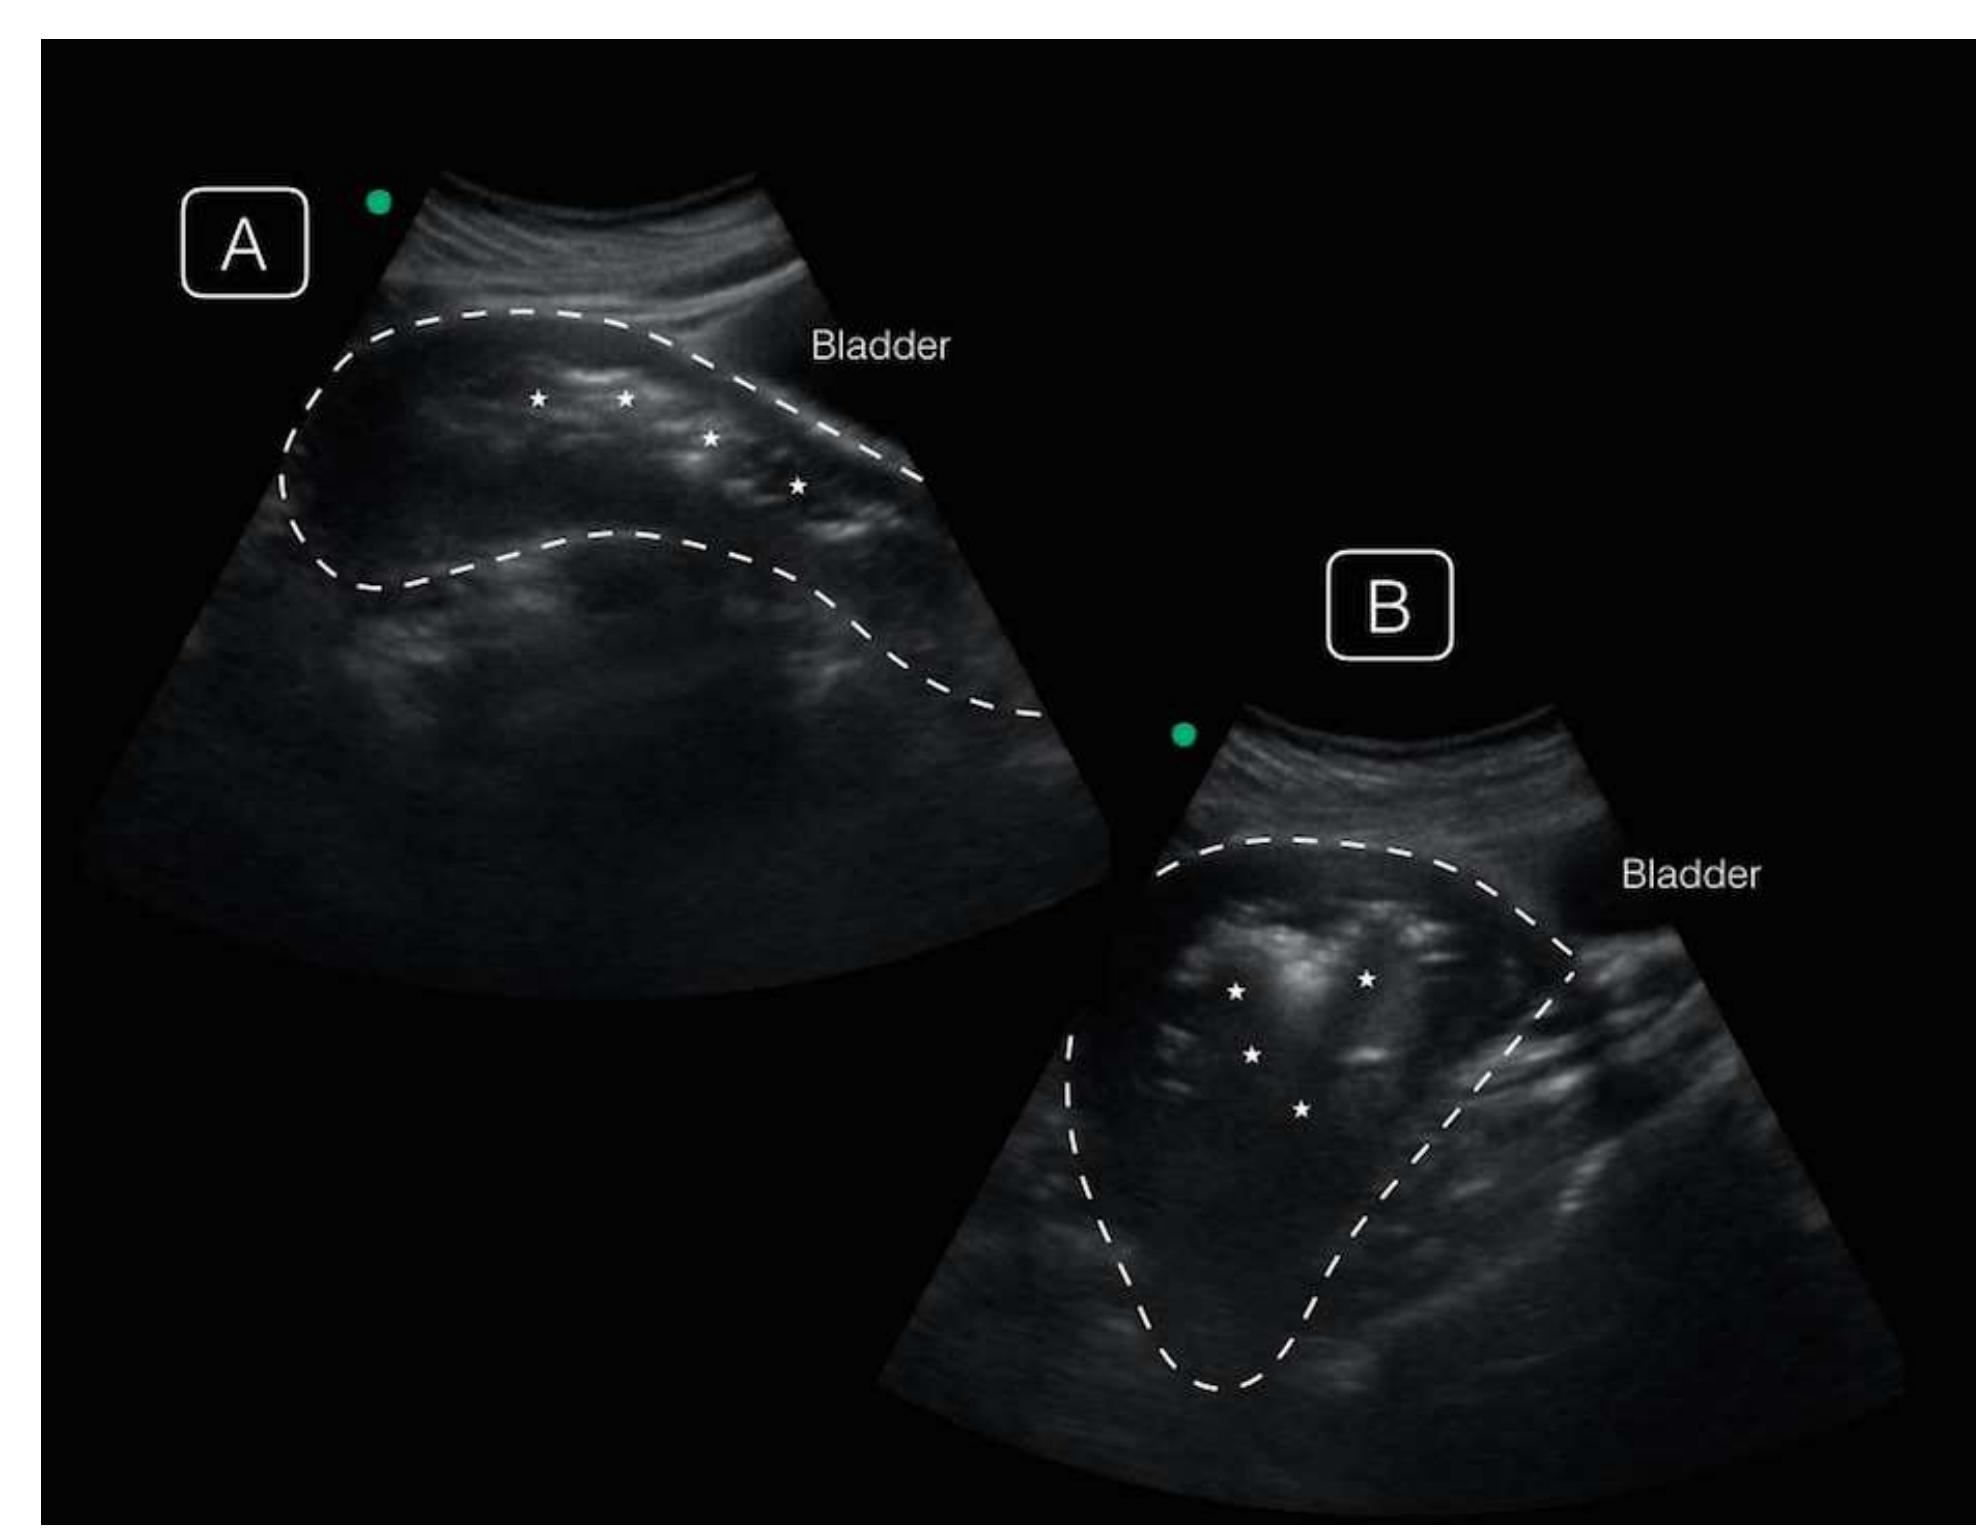

Image. Point-of-care ultrasonographic transabdominal images of the uterus in midline (A) and off-axis sagittal views (B), demonstrating an enlarged uterus (dotted line) with irregular echogenic endometrial debris (asterisk) casting... more